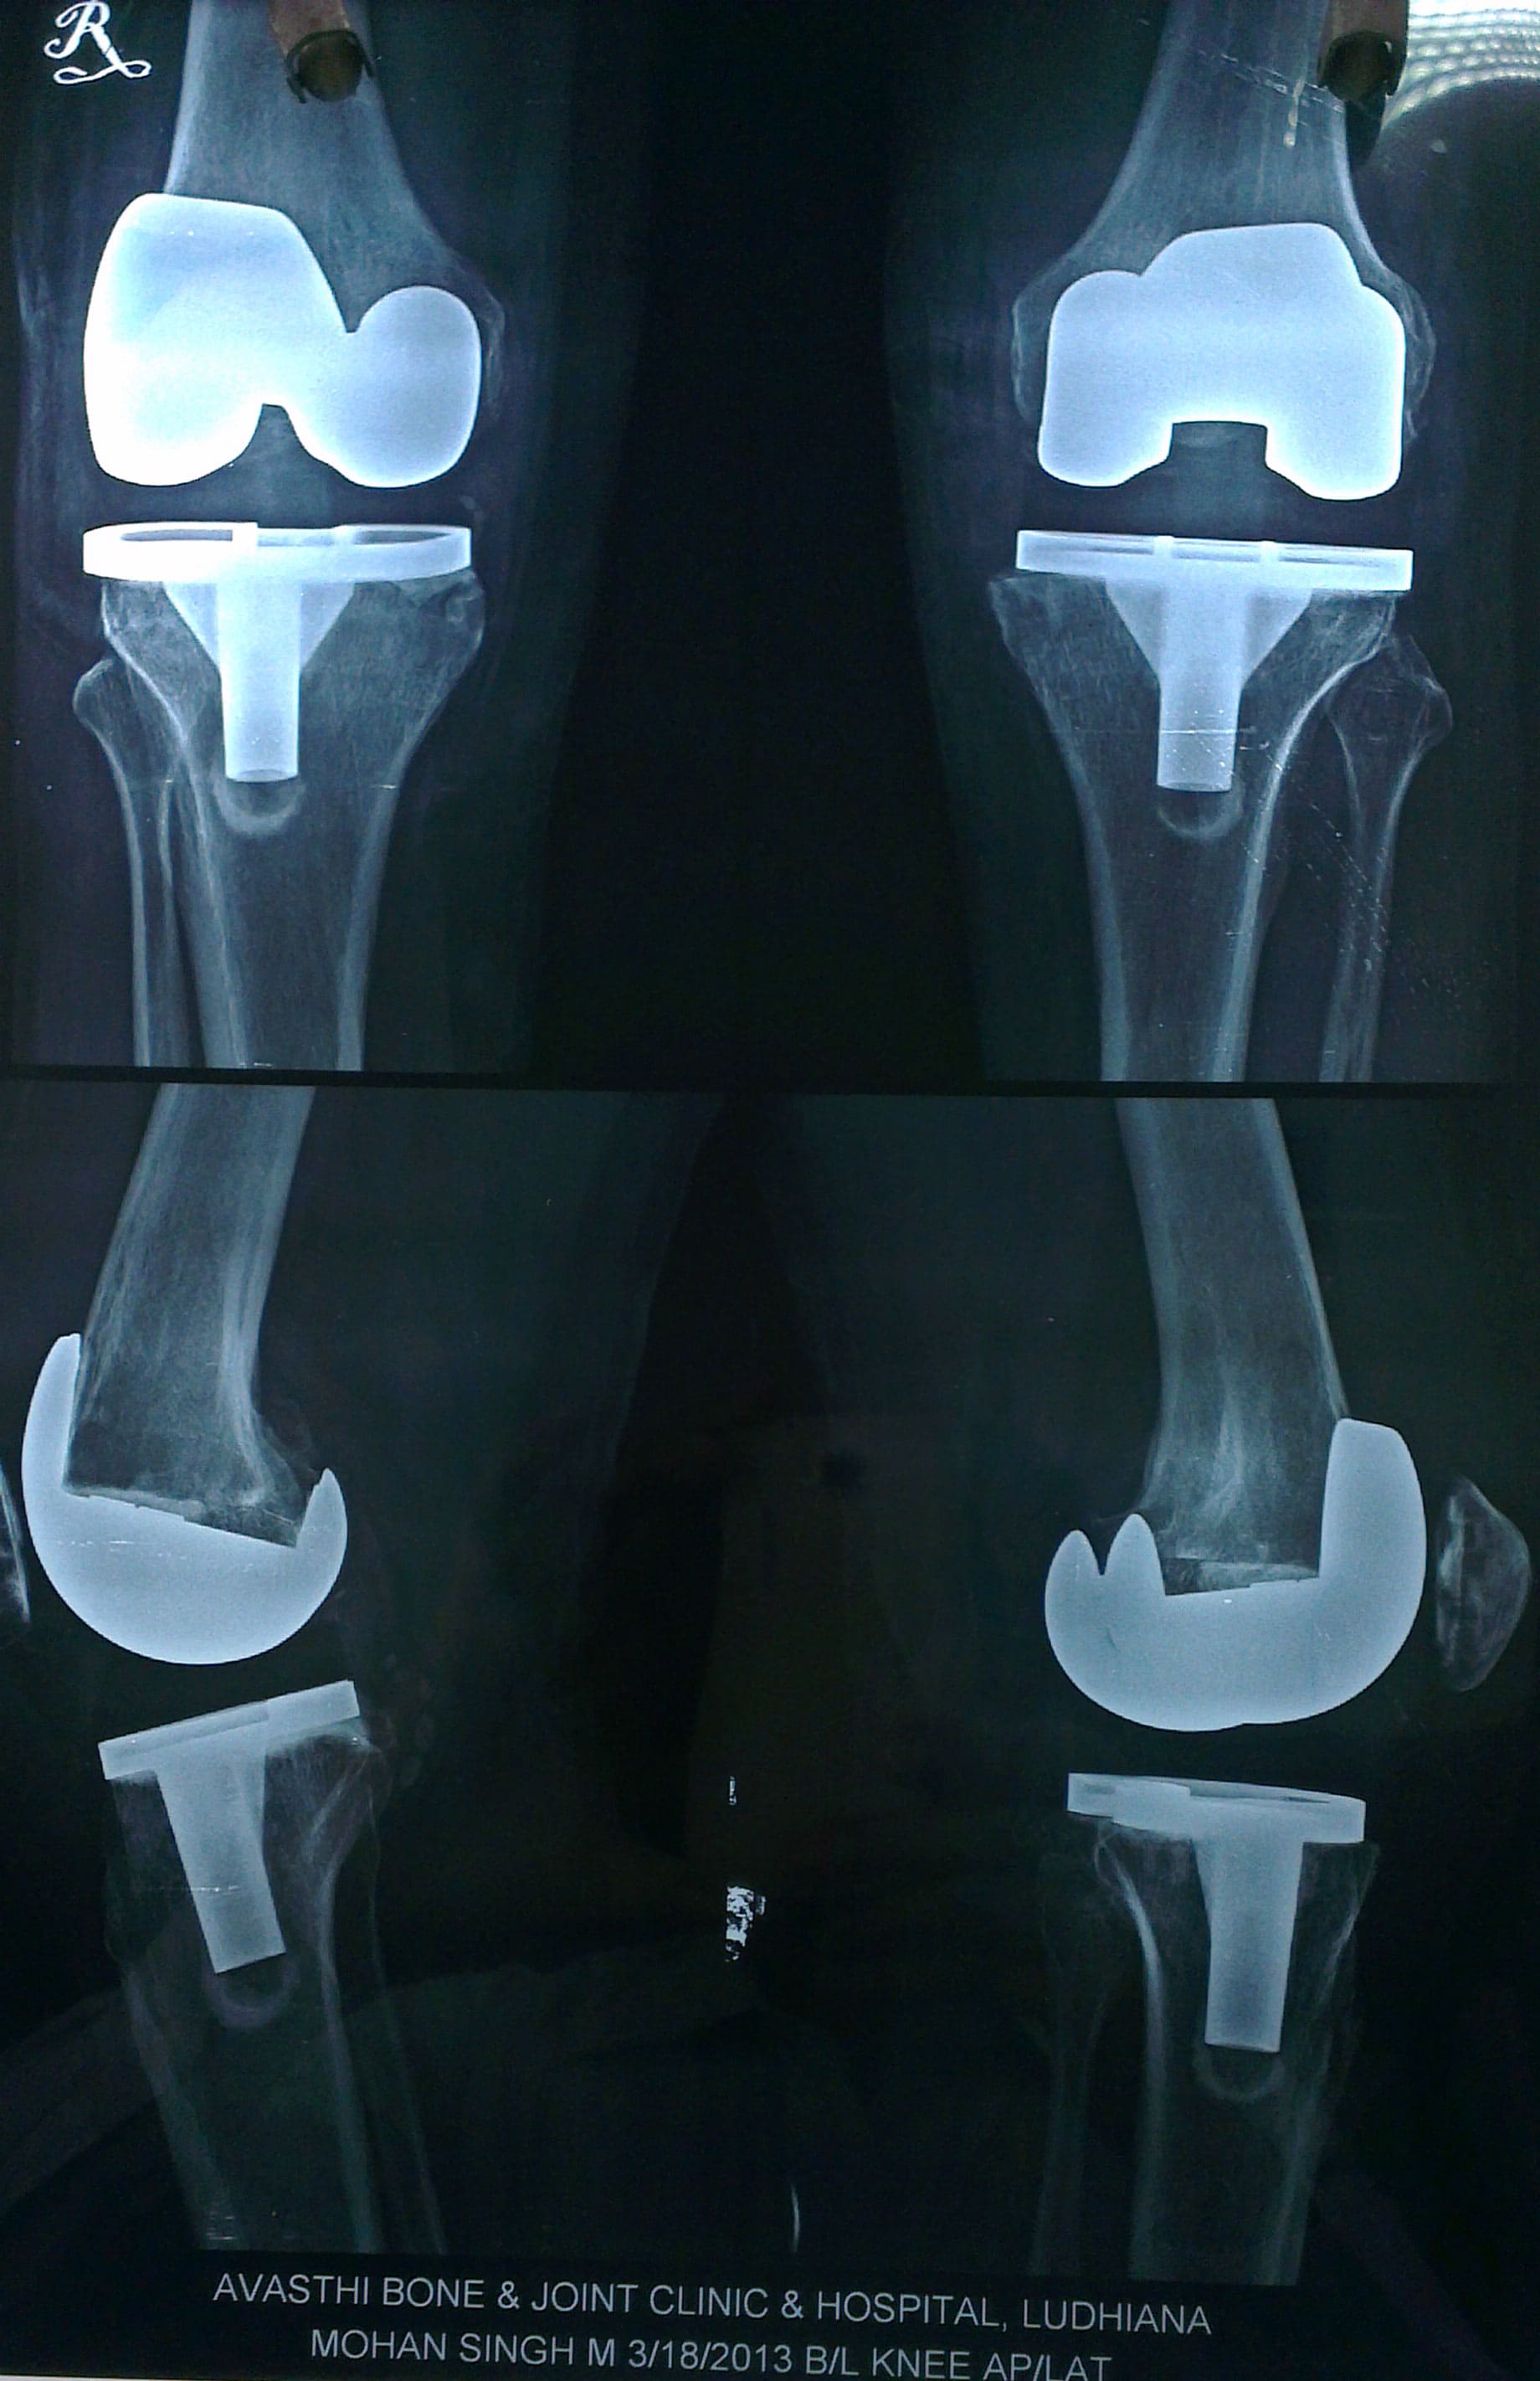

Total knee replacement is a surgical procedure in which injured or damaged parts of the knee joint are replaced with artificial parts.

The procedure is performed by opening up the knee capsule and removing the ends of the thigh bone (femur), the shin bone (tibia), and the underside of the kneecap (patella). Artificial parts are cemented into place and make up the new knee joint.

The new knee consists of metal implants on the ends of the shin bone and thigh bone, and a plastic trough in between them.

The new knee consists of metal implants on the ends of the shin bone and thigh bone, and a plastic trough in between them.total knee replacement diagram Cemented into place are metal implants at the top of the shin bone (tibia) and the bottom of the thigh bone (femur). A tray is placed on top of the tibial implant and a button is placed on the underside of the kneecap (patella). Sometimes the patella does not need to be replaced.